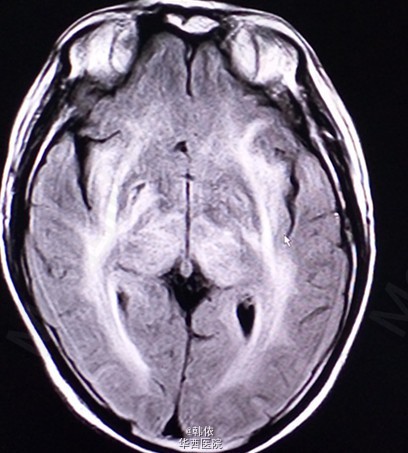

原创:青年男性,因“反复突发意识障碍1+月”入院,1+月前,患者感冒后突发意识障碍,呼之不应,随之出现四肢抽搐,双上肢屈曲、抽搐,双下肢强直,双眼向上凝视,牙关紧闭,小便失禁,无口吐白沫等,持续10+秒后意识恢复,不能回忆,急诊入当地医院治疗,行脑脊液、头部增强MRI等检查,考虑“痫性发作,病毒性脑膜炎”给予降颅内压、抗病毒等治疗,患者住院过程中出现一次右下肢抽动及多次小便失禁,治疗过程中感头部昏沉感,呈持续性,并出现饮水呛咳,治疗效果欠佳。既往患有高血压2+年,未治疗。长期农药接触史2+年。查体:神清,对答切题,高级神经活动正常,双瞳孔等大等圆3mm,对光反射灵敏。四肢肌力肌张力正常,左侧病理征(+),右侧病理征(-),余无特殊。辅助检查:头部MRI示:双侧基底节、双侧丘脑、脑干、双侧小脑及双侧侧脑室旁、双侧半卵圆中心对称性信号异常,考虑中毒性、代谢性疾患可能(见下图)。